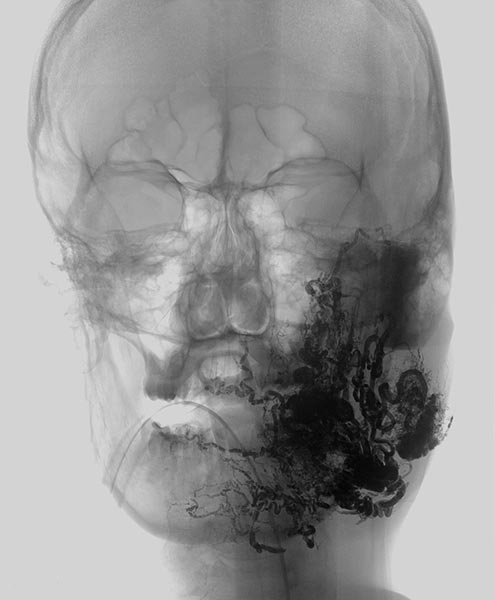

Auffüllung des gesamten Nidus der AVM mittels Ethylen-Vinyl Alkohol-Kopolymer, das in dem hier dargestellten Röntgenbild (a.-p.) als schwarzer, netzartiger röntgendichter Ausguss (sogenannter Cast) innerhalb der verschlossenen AVM-Gefäße sichtbar wird.

Auffüllung des gesamten Nidus der AVM mittels Ethylen-Vinyl-Alkohol-Kopolymer, das in dem hier dargestellten Röntgenbild (seitliche Ansicht) als schwarzer, netzartiger röntgendichter Ausguss (sogenannter Cast) innerhalb der verschlossenen AVM-Gefäße sichtbar wird.